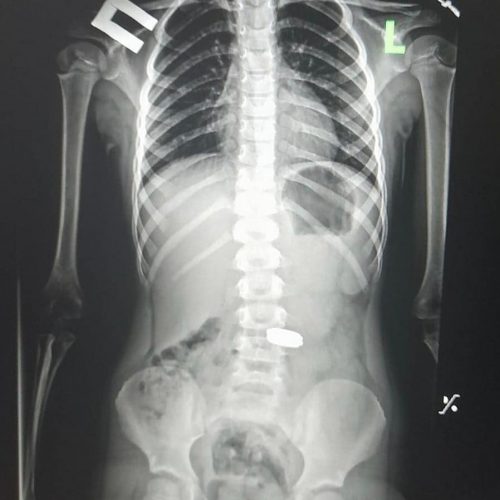

Пять монет из желудка девочки изъяли специалисты Харьковской областной детской клинической больницы №1. Сейчас маленькая пациентка в удовлетворительном состоянии и […]